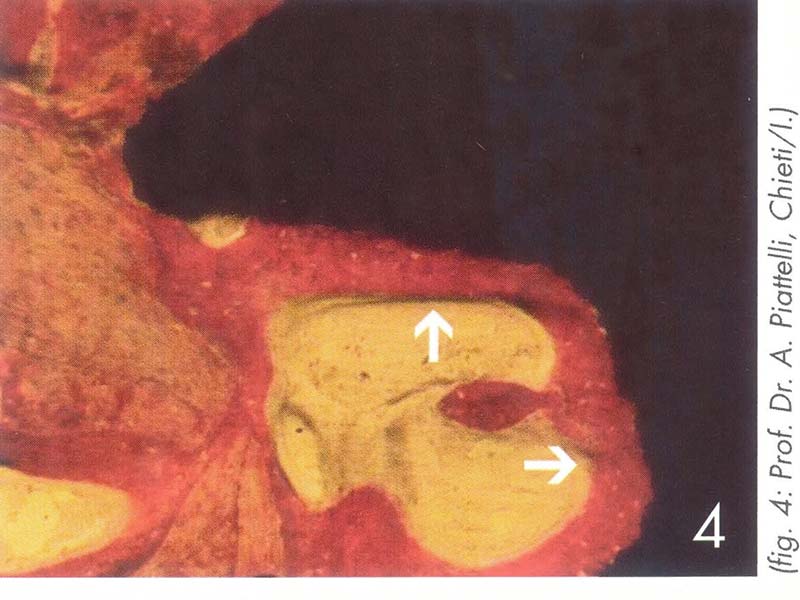

粗糙的植體表面,可以吸引人體纖維母細胞以及骨細胞附著攀爬,進而造成骨頭沉積。

骨細胞在顯微鏡下,沉積在植體表面,進而可以負擔承載假牙咬合的力量,幫助咀嚼。